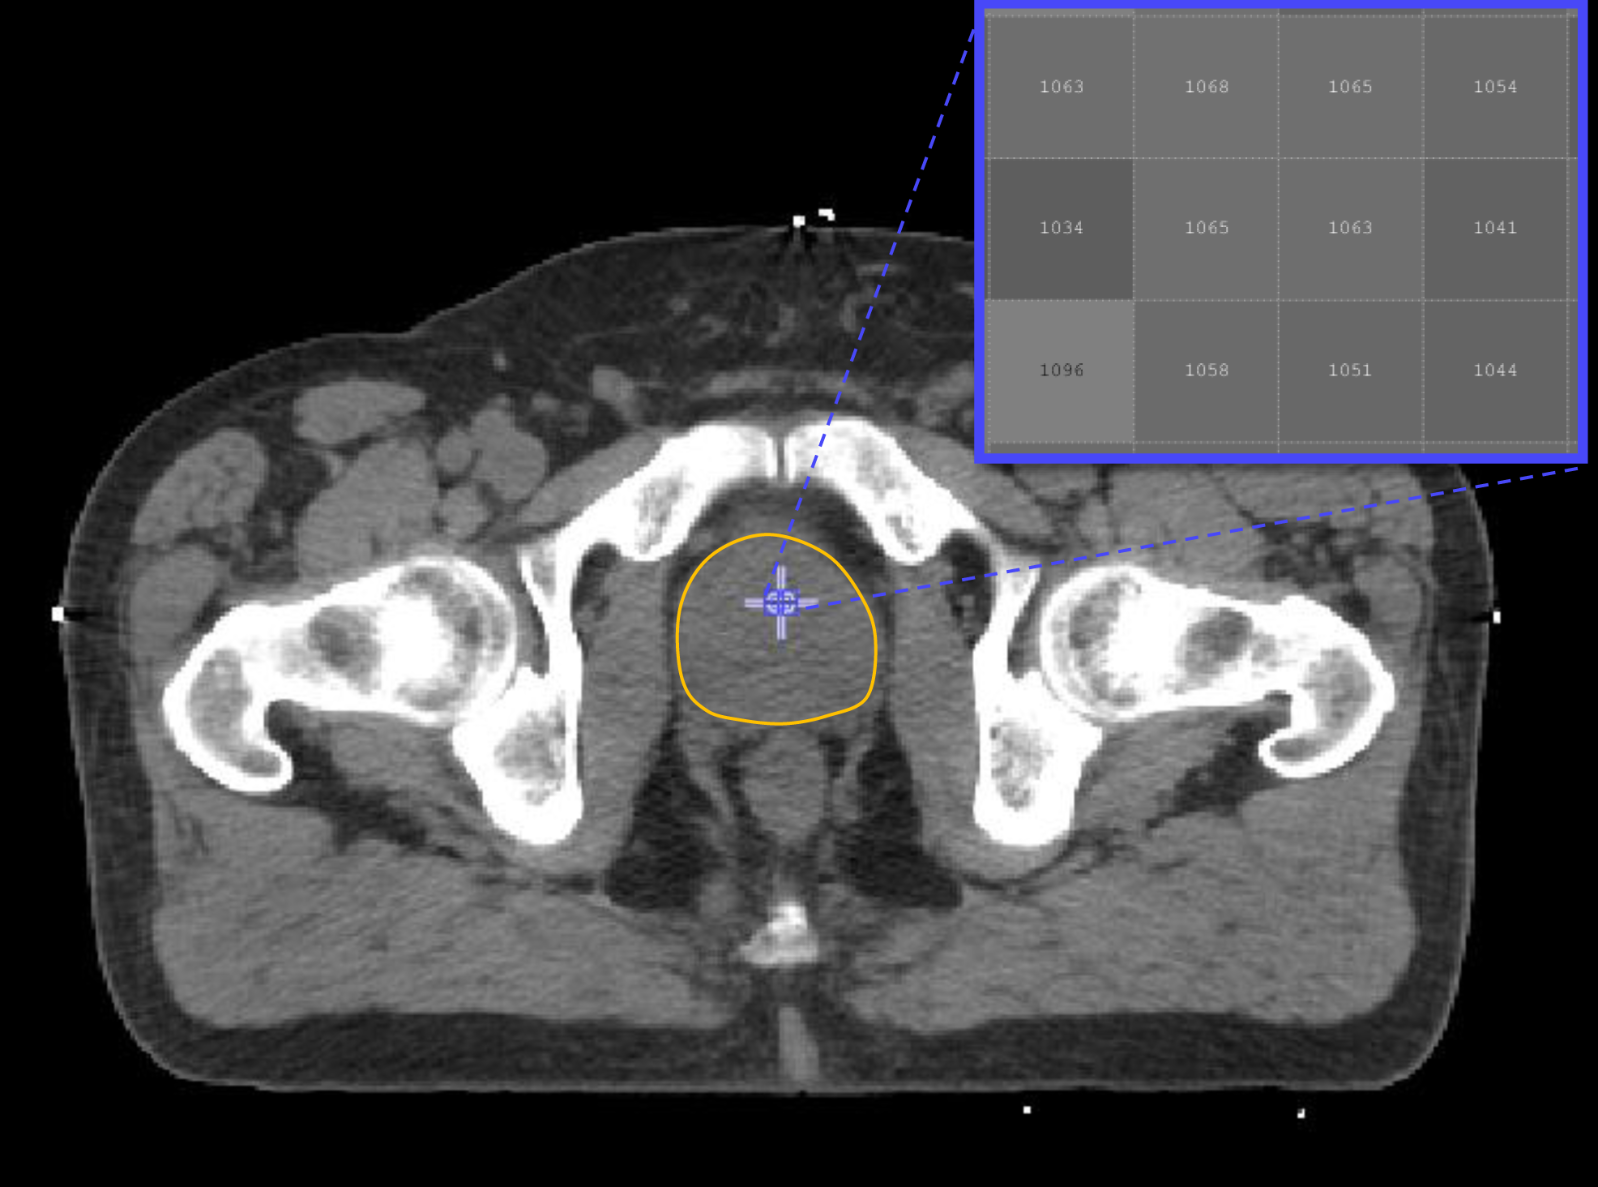

The new method uses images from computed tomography (CT) scans that are routinely collected from all patients. The images are then analysed by a computer to extract hundreds of features, termed ‘radiomic features’, which have the potential to uncover disease characteristics that fail to be seen by the naked eye.

The research team used CT scans for 342 prostate-cancer patients acquired as a routine care prior to radiotherapy treatment. Focusing on the prostate gland, the researchers then extracted and analysed over 500 radiomic features from each image. These features, along with the Gleason score and risk group classification for each patient, were used to ‘train’ a computer to be able to discriminate between patients in low- and high-risk groups, and between those with low and high Gleason score.

CT-based classification models proved able to discriminate between patients from different Gleason score and risk groups. The system was especially competent at distinguishing between patients in low- and high-risk groups, and between those with low and high Gleason score.

Professor Philippe Lambin from the Maastricht University and one of the co-inventors of Radiomics added: “Typically, there isn’t a huge amount of quantitative data in radiology reports. With the radiomics revolution, we need to look at medical images not just as pictures, but as quantitative data potentially useful for trials and routine care.”